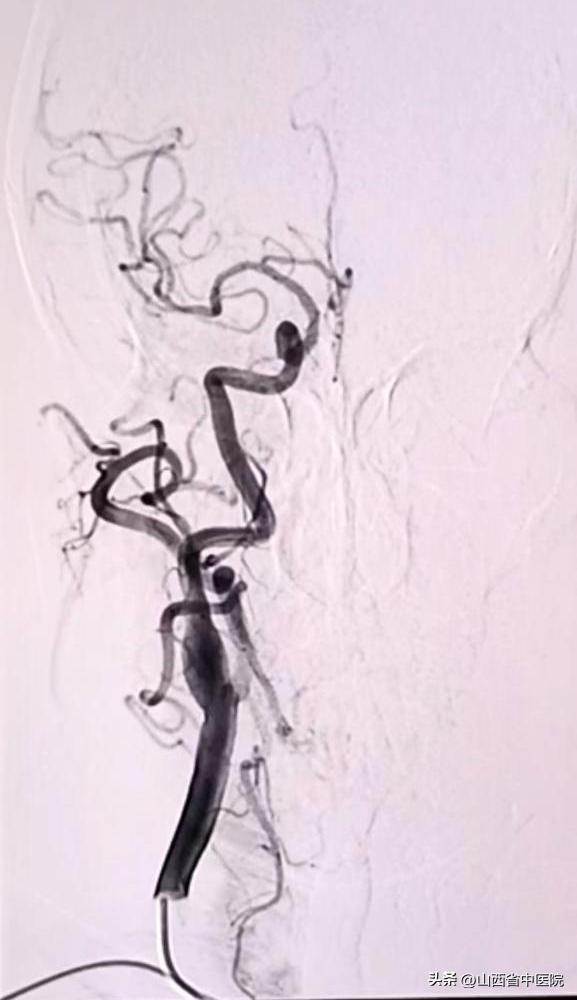

患者短时间内反复脑梗塞,肢体功能缺损严重,既往高血压病史30余年,2型糖尿病史5年余,如果真存在左侧大脑中动脉局限性狭窄,采取血管内治疗可能会帮助患者改善预后。经过科室讨论,决定为该患者进行了DSA检查明确病因。脑血管造影结果显示患者右侧大脑中动脉并未存在明显狭窄,左侧大脑中动脉纤细。因此,考虑患者脑梗塞原因为穿支病变,多次脑梗塞病因终于得以明确。随后经过规范的抗板降脂稳斑治疗,结合焦氏头针、经颅磁刺激治疗、药物扶阳罐及中药联合治疗,患者疗效显著。出院查体,患者下肢肌力恢复至4级,上肢3级,生活能够自理。